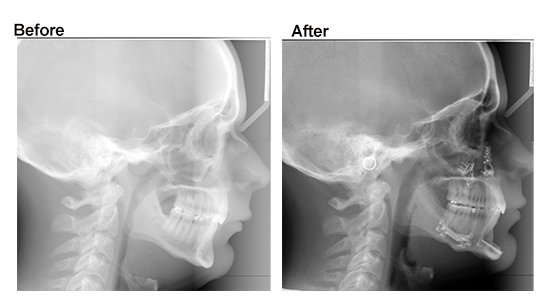

Bimax (bimaxillary osteotomy) is one of the most life-changing maxillofacial surgeries out there. It’s primarily performed to correct skeletal discrepancies, sleep apnea, extreme TMJ related problems but the aesthetic benefits (improved facial harmony) are what draw most people to it. However, the path to getting it — especially covered by insurance — depends heavily on your country, diagnosis, and documentation.

• Bimax (bimaxillary osteotomy) involves repositioning two jaws — the upper (maxilla) and lower (mandible) — to correct bite issues, facial imbalance, or airway problems.

Bimax involves repositioning both the maxilla (upper jaw) and mandible (lower jaw).

It’s typically done for:

• Severe overbites / underbites

• Open bite

• Crossbite / asymmetry

• Sleep apnea (airway obstruction)

• Jaw misalignment causing chewing/speech issues